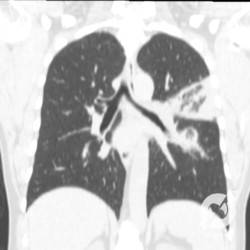

Os agentes etiológicos infecciosos são variados (bactérias, vírus, fungos, parasitas…), mas o que ocorre nos pulmões durante uma infecção por qualquer tipo de agente é a substituição do ar alveolar por secreção (pus, muco, eventualmente sangue ou necrose…) e com isso a manifestação radiográfica vai ser a mesma já que todas estas secreções apresentam a mesma densidade radiográfica: partes moles.

E o nome dado a esta alteração radiográfica que corresponde à substituição do ar alveolar por líquido é a consolidação alveolar.

Uma consolidação alveolar é, por definição, uma opacidade (imagem densa, branquinha) homogênea ou às vezes heterogênea (pela presença de calcificações ou cavidades), de limites mal definidos, exceto quando toca a pleura da parede ou das cissuras pulmonares. É um termo usado tanto em radiografia, como em tomografia computadorizada. Na tomografia, um outro termo é usado: vidro fosco, que é uma opacidade (branquinha mas não tanto como a consolidação), que borra o pulmão mas deixa ver os vasos de permeio (igual bigode de adolescente: dá pra ver todo o fundo).

Nós vamos mostrar aqui um pequeno apanhado de pneumonias de variados agentes, em diversos segmentos e lobos pulmonares, com extensões variadas. O objetivo é identificar o padrão radiológico de consolidação alveolar e não determinar o agente infeccioso, isso vai ser assunto para mais adiante. Aliás já antecipo que é fundamental saber localizar a lesão, porque alguns destes bichos gostam de determinados segmentos, alguns tumores também têm as suas preferências, então localização é fundamental. Se localização não fosse importante, um apartamento na beira do mar sairia o mesmo preço de um apartamento de frente pra BR-101, concordam?